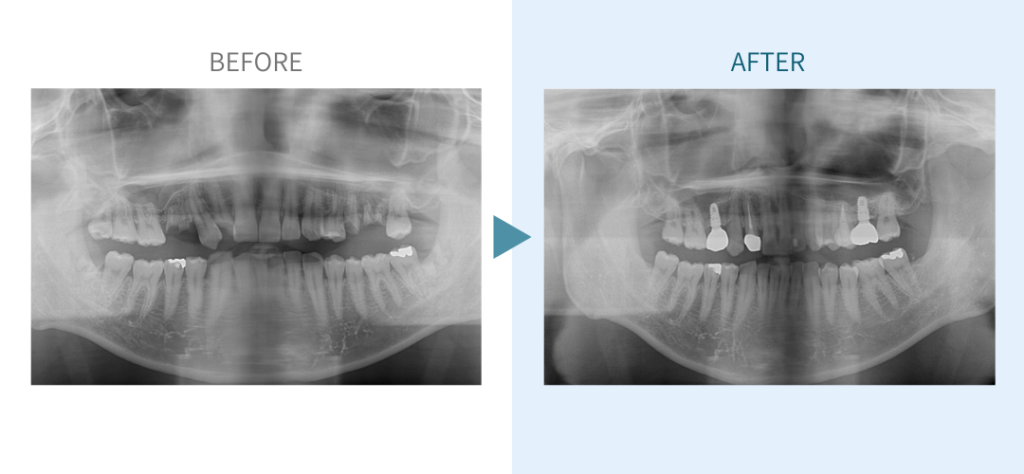

デンタルチームジャパンでは、サイナスリフト(上顎洞底挙上術)や骨造成など、他院で「骨が足りない」と断られた難症例にも対応しています。

私たちは、難症例に関する治療法を学会でも発表しており、その豊富な実績と技術力が評価され、全国から患者様が来院いただいております。

こちらではその一部の症例についてご紹介します。